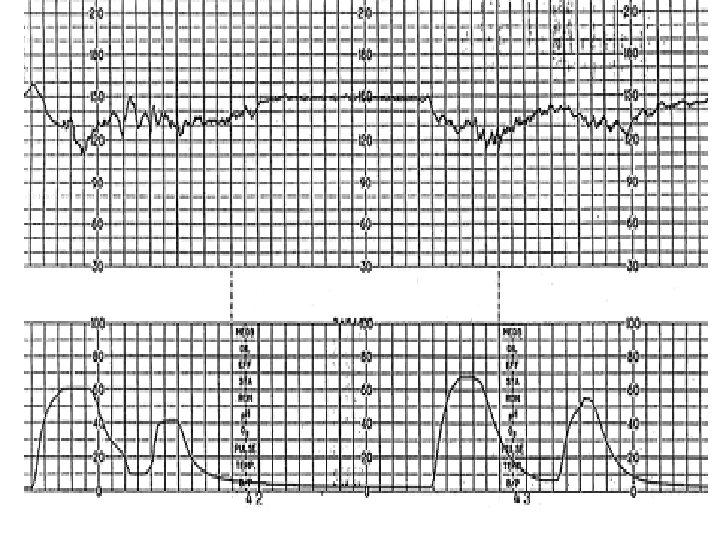

Late Deceleration Gradual decrease in FHR with onset of deceleration to nadir >30 seconds. The nadir of the deceleration occurs after the peak of the contraction

Late Deceleration • Reflex • Myocardial depression